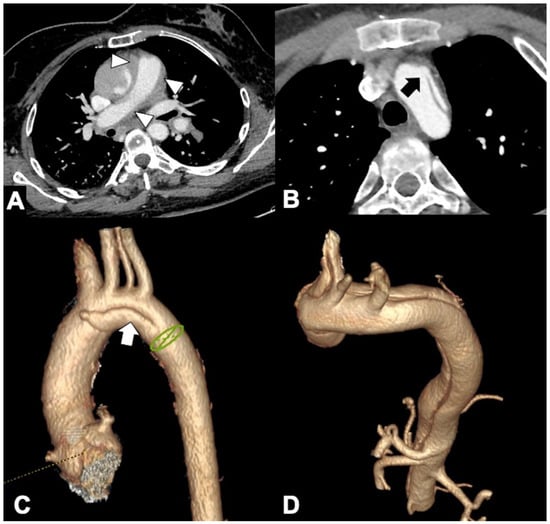

| 2 | Visualization of intimal flap and its extent according to the aortic anatomic segmentation. |

| 3 | The aortic root including coronary artery perfusion and valve function (regurgitation!) and morphology (tricuspid versus bicuspid). |

| 4 | Site, size, and number of the entry tear(s) and all other distally appearing tears including re-entry tears and type and hemodynamic conditions of all side-branch involvement (static or dynamic flow impairment; no flow/low flow). |

| 5 | Diameter, length, course, and CT findings of the false lumen; the aortic maximum diameter, localization, and extent of aortic wall thickening; IMH co-existence. |

| 6 | Patency of all aortic side branches up to the Circle of Willis and caudad to the femoral bifurcation. |

| 7 | Angulation, tortuosity, and precise caliber measurement of all segments of the aorta and iliac arteries; presence of PAU (localization, length, and depth). |

| 8 | Morphologic or hemodynamic signs of organ malperfusion. |

| 9 | Pericardial effusion/tamponade; pleural/extrapleural effusion/hemorrhage; mediastinal hematoma. |

| 10 | Signs of contained (peri-aortic bleeding) or free rupture. |